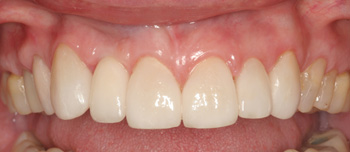

Clinical Cases